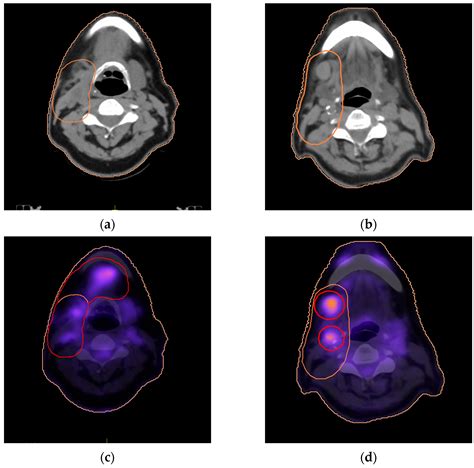

A PET/CT scan—specifically, a Positron Emission Tomography combined with a Computed Tomography scan—is a hybrid imaging technique. While the CT component provides that detailed structural map, the PET scan adds a crucial layer: metabolic function. Before a PET scan, you are injected with a radiotracer, usually a radioactive form of glucose (sugar). Cells in your body that are highly active—such as rapidly dividing cancer cells or inflamed tissues—consume this sugar at a much faster rate than normal cells.

When the PET scanner detects this higher uptake of the tracer, it creates a "hot spot" on the image. By combining the PET (metabolic) and CT (structural) data into one single, fused image, doctors can see not only where a mass is located but also how active it is biologically. This makes PET/CT scans invaluable in:

• Treatment monitoring: Seeing if a tumor is responding to chemotherapy or radiation before it actually shrinks in size.

• Diagnostic clarity: Distinguishing between scar tissue (non-metabolically active) and active tumor tissue (highly active).